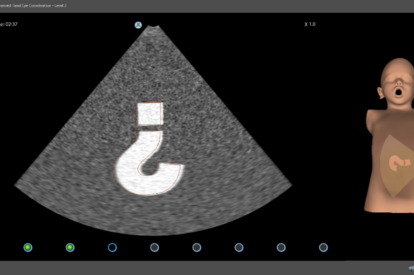

Simbionix Ultrasound Mentor is the answer to the growing need for ultrasound training among multiple medical specialties. This modular simulation platform enables easy manikin rotation (male, female, pediatric and interventional), and offers diverse applications for a range of specialties such as OB/GYN, Point-of-care Ultrasound (POCUS) and Echocardiography.

Ultrasound Mentor accelerates the development of basic to advanced technical and cognitive skills, by providing not only the probe manipulation training, but also a didactic environment enabling structured, self-guided learning including step-by-step instructions and educational aids such as 3D anatomical map and probe positioning assistant, all backed up with our progress monitoring tool MentorLearn.

- Step-by-step tasks provide a self-learning opportunity for sonography skills and scanning protocols

Pediatric Basic Skills Module

Pediatric Abdominal Module

Pediatric eFast Module